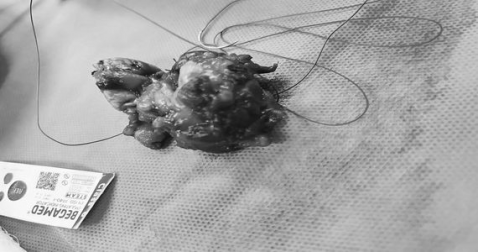

نجاح عملية رفع ورم الغدة اللعابية لمريضة خمسينية في مستشفى القرنة العام بالبصرة

نجح

فريق طبي جراحي في مستشفى القرنة العام بالبصرة بإجراء عملية فوق الكبرى لرفع ورم

كبير في الغدة اللعابية تحت الفك الأيسر لمريضة تبلغ من العمر ٥٣ عاماً وتعاني من

مرض السكري وألم مستمر وتورم في الوجه.

وذكر

اعلام دائرة صحة البصرة :" تم رفع الورم بالكامل تحت التخدير العام، وأُرسل

للفحص النسيجي. بإشراف الدكتور سيف منعم دهيس أخصائي الأذن والأنف والحنجرة،

وبمشاركة الدكتور محمود مؤيد ضمد أخصائي التخدير،.

واضاف:"

نُقلت المريضة إلى ردهة الجراحة العامة للمتابعة، وهي الآن بحالة صحية جيدة،